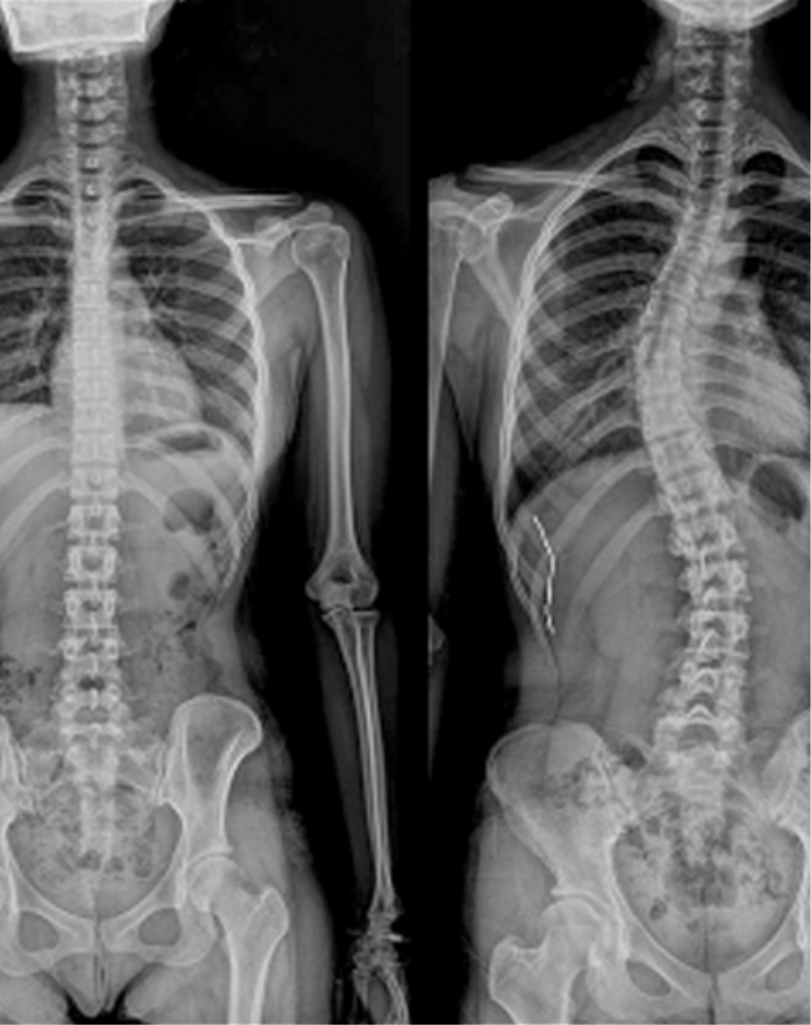

척추측만증

척추가 정면에서 보았을 때 좌우로 휘어진 상태를 말하며,

흔히 S자형 또는 C자형 곡선으로 나타납니다.

성장기 청소년에게 많이 발생하지만,

성인에서도 퇴행성 원인으로 나타날 수 있습니다.

어깨 높이가 다르거나 몸이 한쪽으로 기울어져 보임

골반 비대칭, 갈비뼈 돌출

허리나 등, 목의 만성적인 통증

청소년의 경우 외관 변화 외에 자각 증상이 없는 경우도 많음

X-ray 검사, MRI, C-arm(실시간 영상장비) 유도 하 주사

관찰 및 추적 검사, 운동치료/도수치료, 보조기 착용

수술적 치료 : 40도 이상 중증이거나 통증 및 기능장애 등